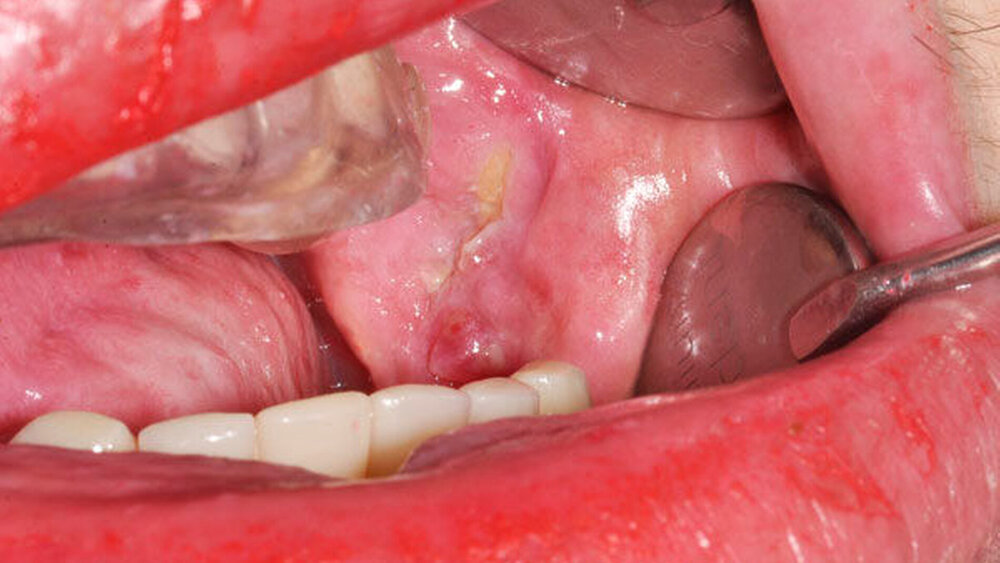

Unter dem Begriff IORN versteht man ein Krankheitsbild, bei dem es durch die Behandlung mit hochenergetischer Strahlung im Rahmen einer Tumortherapie des Kopf-Hals-Bereichs zur Ausbildung umschriebener Nekrosen des Kieferknochens mit Superinfektion durch ortsständige Keime der Mundhöhle kommt. Typische klinische Merkmale sind enorale Schleimhautulzerationen mit chronisch freiliegendem Kieferknochen [Morrish et al., 1981, Beumer et al., 1979; Marx, 1983]. Die Symptomatik ist durch ein variables und schwer klassifizierbares klinisches Bild gekennzeichnet. Zu den IORN bedingten Komplikationen zählen vor allem Beeinträchtigungen der Kau-, Schluck- und Sprechfunktion.

Das klinische Leitsymptom der IORN ist der langfristig (3 bis 6 Monate) inspektorisch und sondenpalpatorisch freiliegende avitale Kieferknochen bei stattgehabter Bestrahlung im Kopf-Hals-Bereich.

Entsprechend der Definition der IORN ist die Diagnosestellung an eine gezielte Anamnese und klinische Untersuchung von Mundhöhle und Perioralregion gebunden. Neben der Inspektion und Palpation umfasst diese auch die Vitalitätsprüfung benachbarter Zähne sowie eine Sensibilitätsprüfung. Der die IORN fachlich behandelnde Arzt beziehungsweise Zahnarzt legt Ausmaß und Umfang der Diagnostik (dreidimensionale Bildgebung) fest. Das Orthopantomogramm (OPTG) weist im Vergleich zu schichtbildgebenden Verfahren (Computertomografie, Magnetresonanztomografie) eine reduzierte Sensitivität auf [Store und Larheim, 1999]. Wichtigste Differenzialdiagnose der IORN ist ein malignes Geschehen (zum Beispiel Rezidiv, Metastase), weswegen eine histologische Sicherung erfolgen sollte [Marwan et al., 2014].